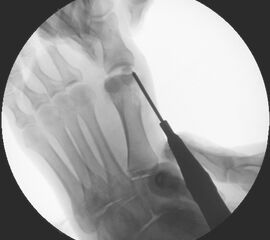

• Positionierung des Bildwandlers: 90° Winkel zum Os metatarsale I. Benötigt wird die Durchleuchtung des Vorfußes a.p., seitlich und schräg.

Operationstechnik

Der von Isham/Reverdin beschriebenen minimal invasiven Technik zur Korrektur einer Hallux valgus Deformität liegen 4 Operationsschritte zu Grunde:

4. Akin Osteotomie der Großzehengrundphalanx

Die Folge der Operationsschritte sollte strikt von 1. - 4. erfolgen, da ansonsten die mediale Closing Wedge Osteotomie bei vorzeitigem lateralem Release und/oder Akin Osteotomie nicht geschlossen werden kann. Nach der von Isham beschriebenen Originaltechnik finden Implantate keine Anwendung, zur Sicherung und besseren Fixation können osteosynthetische Verfahren angewandt werden (siehe auch Fehler, Gefahren und Komplikationen).